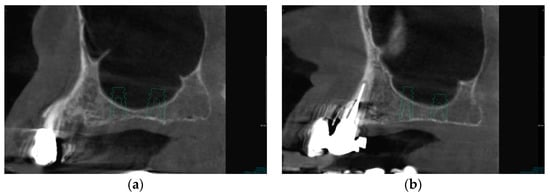

1. Introduction

2.6. Case Study